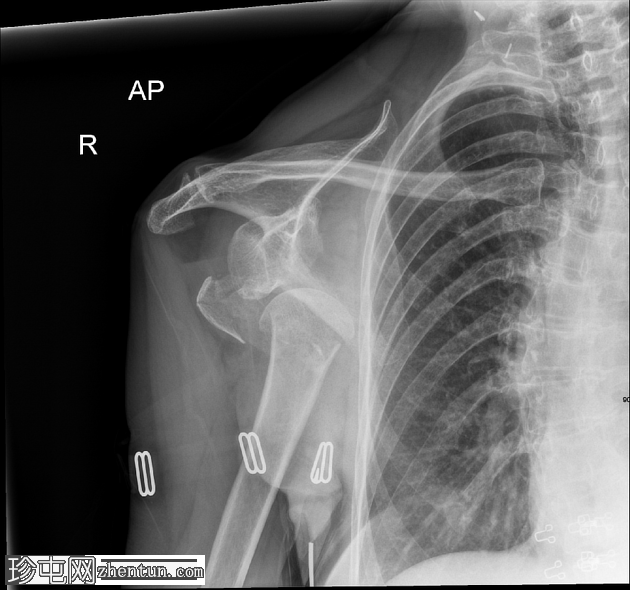

X线片

1.png

正位

右肱骨近端粉碎性骨折,严重移位,累及肱骨颈和肱骨大结节,伴肱骨近端相对于肩胛盂的前下脱位和肩关节脂肪血肿。肩锁关节完整;另可见胸椎侧弯、右侧颈部手术夹以及覆盖上臂和腋窝的衣物痕迹。

该X线片显示右肩高能量损伤,表现为肱骨近端粉碎性骨折,严重移位,累及肱骨颈和肱骨大结节。伴随的前下肩关节脱位反映了稳定软组织结构的破坏,这是此类骨折脱位模式的常见特征。脂肪血肿的存在表明骨折已延伸至关节内,骨髓脂肪渗入关节腔;这是评估损伤严重程度的重要影像学线索。